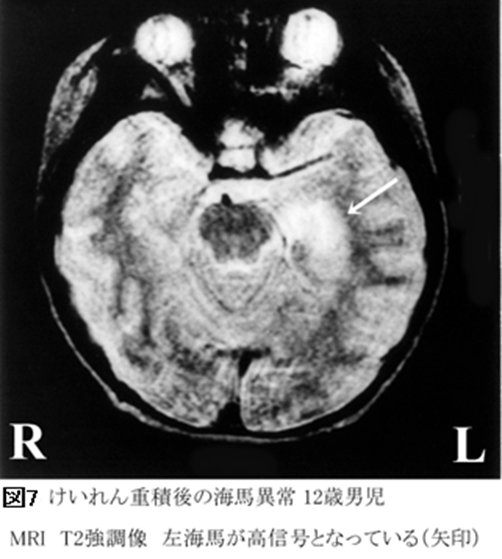

実際、動物実験でも、熱をともなうけいれん重積が海馬の神経網を変化させ、将来、そこがてんかん焦点になりうることが確認されています。さらには、ヒトにおいても、重積けいれんが海馬に異常をもたらす可能性が、MRI検査で確認されています(図7)。

未解決の問題――熱性けいれん重積発作と内側側頭葉硬化てんかん.

未解決の問題――熱性けいれん重積発作と内側側頭葉硬化てんかん

遷延する熱性けいれんがみられたあと、ある程度期間をおいて発症してくる内側側頭葉硬化てんかんです。

ただし、HHE症候群と異なり、内側側頭葉硬化てんかんの患者さんは、けいれん後、半身麻痺が残るわけではありません。長いけいれんはあったものの、一見、うまい具合になんの問題も残さずにけいれんは終わってしまったようにみえます。しかし、遷延する熱性けいれんを起こしてからかなり年月がたってから、難治てんかんとなってしまうのです。そして、よくよく調べてみると、何も傷跡を残さず治ったはずなのに、側頭葉の内側が硬く小さく縮こまっていることに気づかれます。